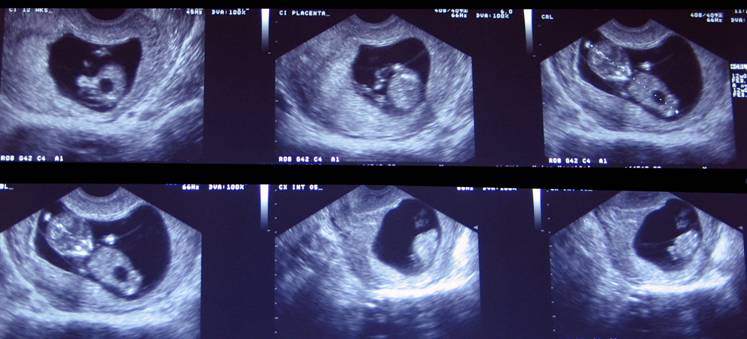

Trisomy 18 – Megacystis 9 mm at 12 weeks of gestation